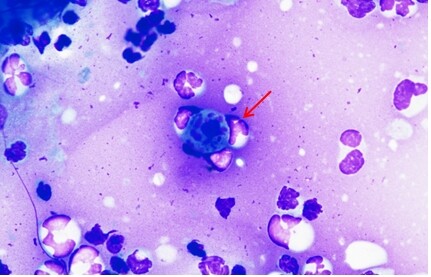

Un cas de cryptococcose féline

Saton est un chat européen mâle castré de 7 ans, présenté en consultation pour de multiples masses sous cutanées sur l’abdomen et hypertrophie des nœuds lymphatiques inguinaux.